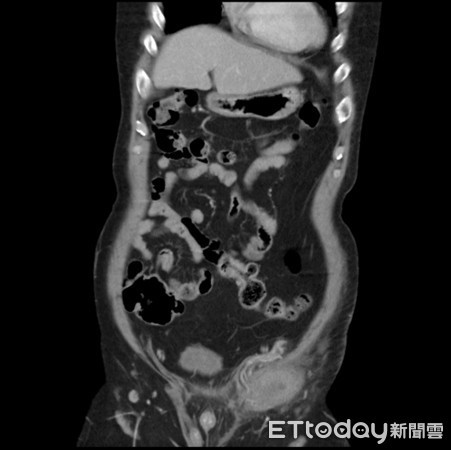

Theo trang Ettoday, một người đàn ông 46 tuổi ở thành phố Cao Hùng, Đài Loan đến bệnh viện trong tình trạng đau bụng dưới bên trái cấp tính. Sau khi khám, bác sĩ nghi ngờ bệnh nhân bị thoát vị bẹn trái và có thể bị hoại tử ruột. Tuy nhiên, sau khi tình cờ thấy bệnh nhân không có tinh hoàn, bác sĩ cho tiến hành chụp cắt lớp thì phát hiện ra phía bên trái tinh hoàn đang bị hoại tử. Do đó, bệnh nhân được chẩn đoán là bị tinh hoàn lạc chỗ, cần phải phẫu thuật khẩn cấp và may mắn là đã vượt qua cơn nguy hiểm.

Tố Kim Minh, trưởng khoa Tiết niệu, bệnh viện thành phố Cao Hùng cho biết: “Tinh hoàn lạc chỗ (Cryptorchidism) là do sự gián đoạn của tinh hoàn từ khoang bụng xuống bìu trong quá trình phát triển của nam giới. Điều này nghĩa là tinh hoàn không di chuyển vào đúng vị trí trong bao da treo phía sau dương vật trước khi bé trai ra đời".